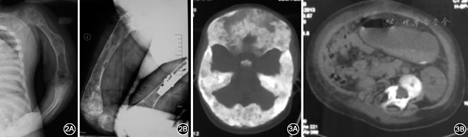

患者X线片表现2A左侧肱骨、桡尺骨、弥漫性骨质破坏,骨干膨胀性囊性改变 2B股骨弥漫性骨质破坏,骨干膨胀性囊性改变,右股骨内固定术后改变

图3

患者CT检查结果  3A颅骨、颌面骨弥漫性骨质增厚,骨质内见多发磨玻璃样、虫蚀样骨质破坏 3B脊柱CT显示脊柱侧弯畸形,脊柱椎体及附件骨质内见多发磨玻璃样、虫蚀样骨质破坏